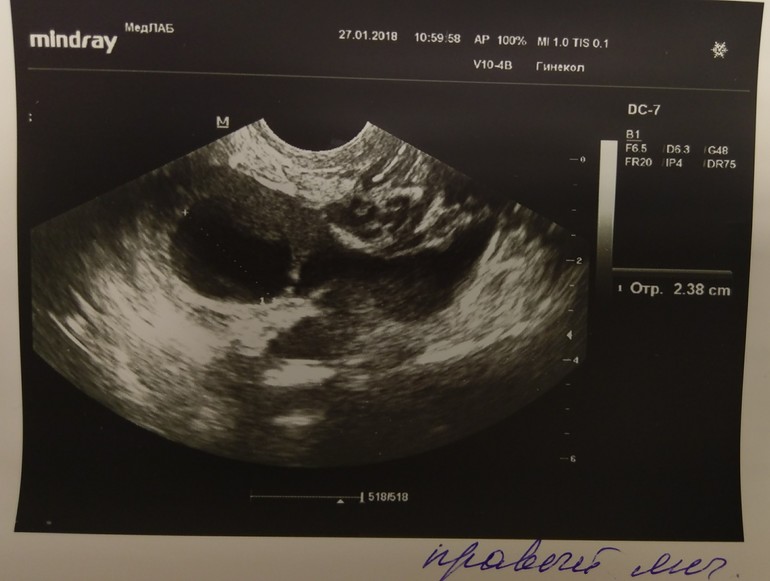

24 дц беременность